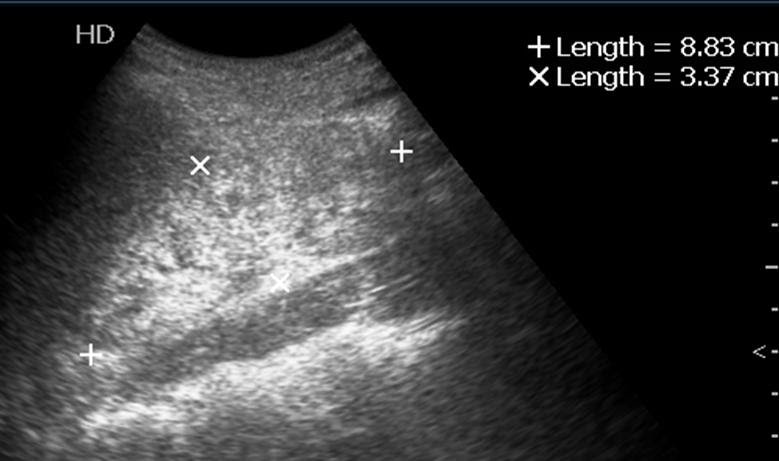

Ultrasound findings in renal parenchymal disease: Local symptoms are less present mild abdominal pain, hiding the causal disease; Nycturia with oliguria during day. Renal parenchymal hypertension is a form of secondary hypertension caused by kidney disease. The most common causes of renal parenchymal disease are diabetes and high blood pressure. Renal parenchymal disease and hypertension. Try our symptom checker got any other symptoms? Fish fish is recommended for one with bilateral renal parenchymal disease.